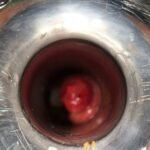

LASER LIAS FOR ANAL FISSURES AND BANDING OF HEMORRHOIDS